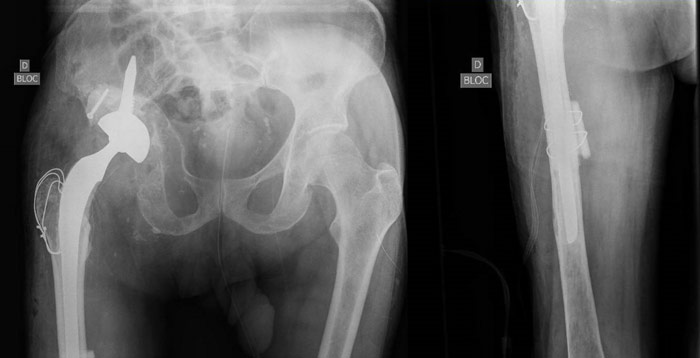

Pre-op x-ray